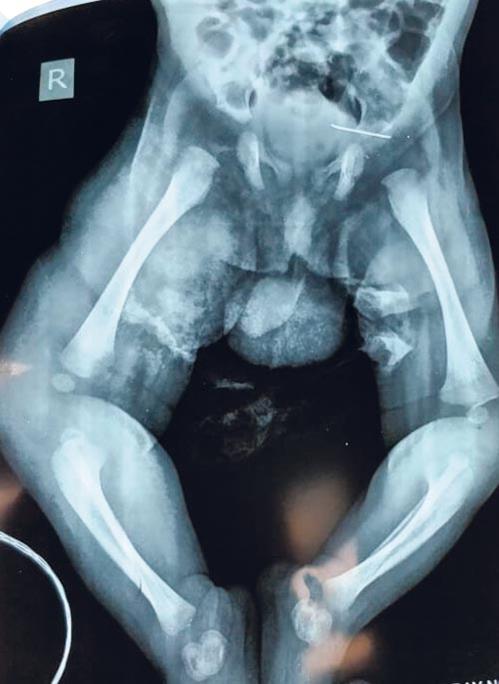

The 2 cm needle was embedded in the capsule of the left hip joint

As the treatment for osteomyelitis was started on the baby for (bone infection), doctors found a foreign body in the left buttock region through an x-ray. It was first considered as an artifact, but the foreign body shadow persisted on subsequent x-rays so a CT scan was done. It was then concluded that the foreign body was part of a needle used to give vaccinations. The operation to remove the foreign body took place on July 10.

“The broken vaccine needle was inside his body for 19 days. He was lucky that it has not harmed him and he could not express his pain. After discussing with his parents, it was decided to remove the needle. The baby was taken up for intra-operative surgery for removal of the foreign body. It was difficult to find the exact location, hence multiple x-rays were done to find the position of the needle. It took two hours to remove the needle under C-arm guidance localisations. The 2 cm needle was found embedded in the capsule of the left hip joint and the baby has recovered without any complications,” Dr Pradnya added.